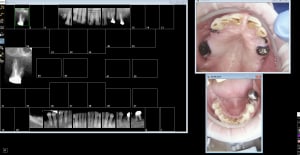

Non_endo_4_2019-09-03_19.24.15_tarfev.png